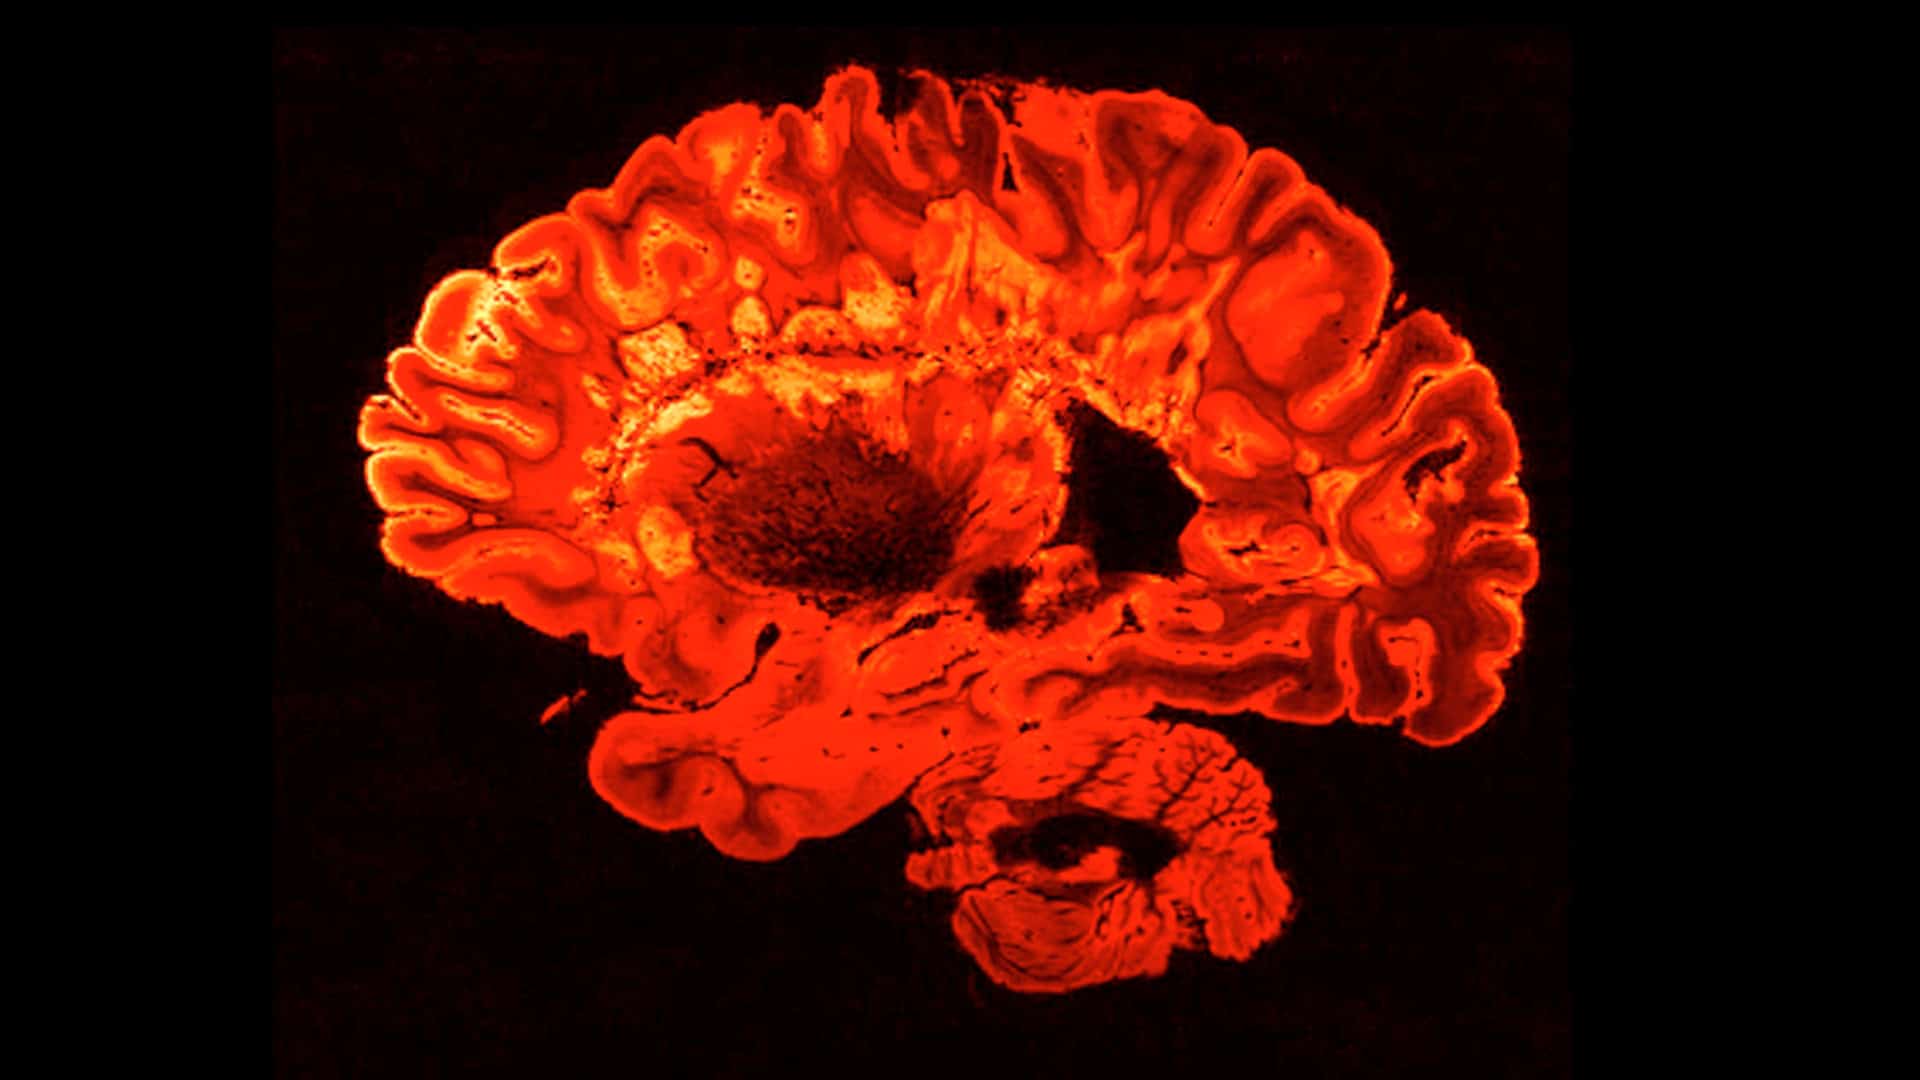

Malia Politzer: After playing the game, the participants lie down in a functional magnetic resonance imaging machine, fMRI, which captures blood flow in the brain.

Nafees Hamid: Depending on where it goes, you can make an inference that that part of the brain is more active for that particular task.

Malia Politzer: While the participants rank these values, the fMRI machine is recording what is happening in a particular part of their brain.

Nafees Hamid: This is a part of the brain; it’s called the left inferior frontal gyrus. It’s oftentimes used for rule processing. It’s normally active when people are processing sacred values. But what we found was that people who were socially excluded, now for their non-sacred values this part of the brain came online.

Malia Politzer: After getting out of the fMRI, the participants retook the survey. They had a choice; they could change their rankings to align with those of their peers, or they could keep them the same. The scientists looked at two specific regions of the brain, one involved in self-reflection and another involved in subjective values.

Malia Politzer: The ARTIS team says that when these active supporters of an extremist group were processing their sacred values, the part of the brain associated with deliberation shut down. And they say it wasn’t working in tandem with the part of the brain associated with subjective values anymore.

Patricia Churchland: Now having said that, it is of course something that the researchers recognize, and that we all recognize, and that is that using functional MRI to explore these kinds of phenomena is the best we can do right now, but it isn’t wonderfully good. You can see some differences at, shall we say, a gross level, and they are significant. But for us to go deeper, we need better kinds of tools to explore the human brain.